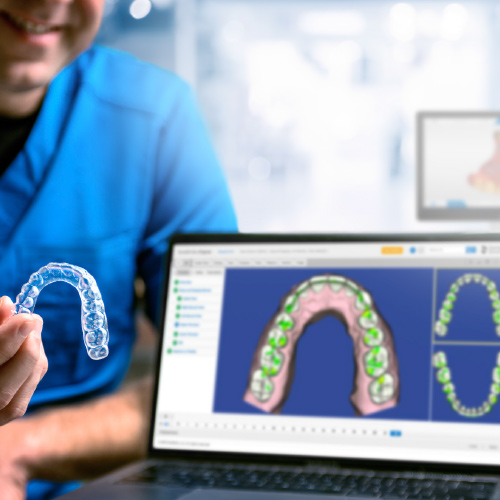

Taking Digital Orthodontics to the Next Level

Lisa Alvetro, DDS, MSD

Tuesday, July 28, 2020

Implementing digital orthodontics in-house offers a practice many options that will increase your services, patient experience, accuracy, and cost effectiveness. In this educational eBook, Lisa Alvetro, DDS, MSD, demonstrates real-world applications of digital orthodontics in her practice, including...